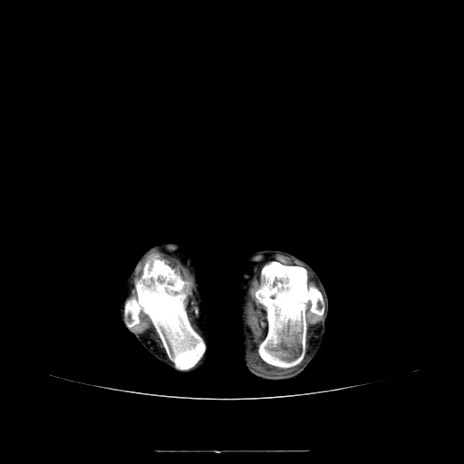

【症例】70歳代女性

【主訴】お腹が張る

【現病歴】1週間くらい前から腹部膨満の自覚あり。昨日夜から増悪したため、本日救急外来受診。

【身体所見】意識清明、BT 36.5℃、BP 165/106mmHg、HR 80bpm、SpO2 98%、腹部:膨満、軟、自発痛・圧痛なし、触診にて不快感あり、腸蠕動音:減弱

【データ】WBC 12600、CRP 1.04